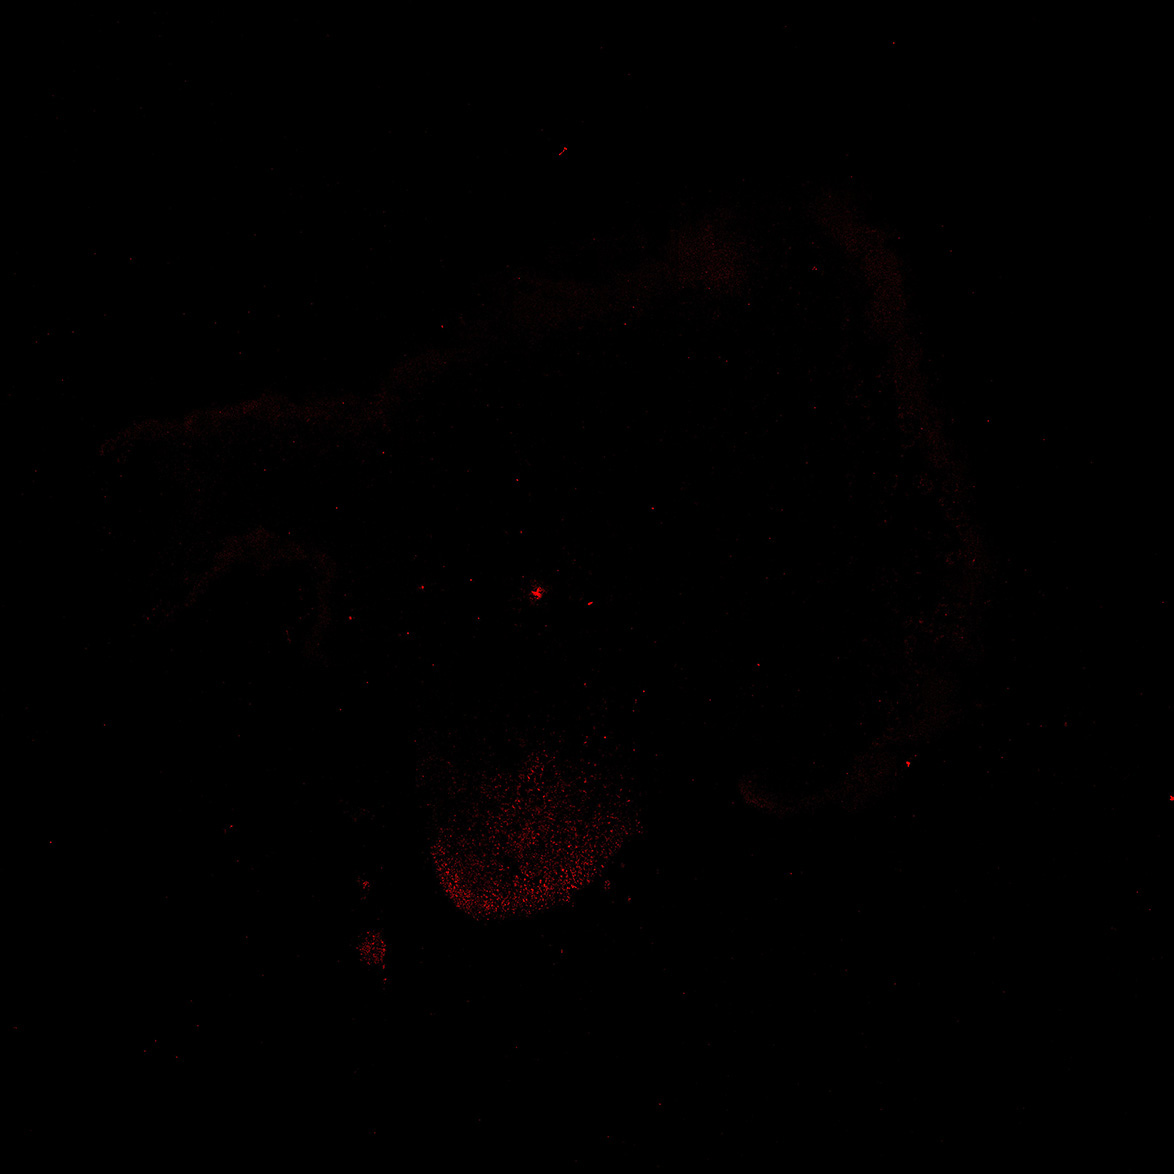

TH

11PCW human midbrain